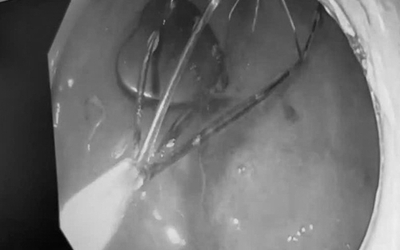

Người đàn ông 36 tuổi bị tiểu buốt, đi khám các bác sĩ phát hiện "bí mật đáng sợ"

Các bác sĩ Khoa Ngoại Tiết niệu, Bệnh viện Đa khoa tỉnh Thanh Hóa vừa xử trí thành công một trường hợp dị vật bàng quang hi hữu.